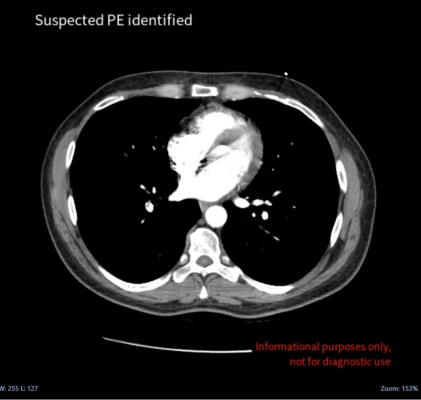

February 22, 2023 — Medical imaging AI specialist Avicenna.AI announced the launch of CINA-iPE, a CE-marked AI tool that analyzes images from chest CT scans for the presence of incidental pulmonary embolism. CINA-iPE is the first tool in CINA Incidental, a new suite of medical imaging solutions from Avicenna.AI that detect unsuspected pathologies on CT scans.

Incidental pulmonary embolism is a frequent finding on routine CT scans of the chest, but only 25% of incidental emboli are reported at the initial interpretation. Delayed and missed findings are some of the most serious problems in diagnostic imaging, and incidental pulmonary embolism is a significant cause of mortality in the cancer patient population.